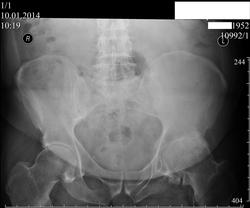

Неоартроз.

Вторичный коксартроз слева 3 ст. сомнений не вызывает.

99% травма - неартроз остеофитов.

По теме - на Rg на мой взгляд остеонекроза нет. Имеет место коксартроз как исход комбинированного импинджемента с обоих сторон. Экзстоза на шейке образовался в результате конфликта с нижней частью вертулжной впадины (coxa profunda)? чему способствовала диспластичная нижняя часть вертлуги. Седалищный бугор деформирован за счет этой же дисплазии. Да, дисплазия - это не только неглубокая вертлужная впадина.

Андрей, спасибо за высказанное мнение, (несколько альтернативное к остальным, в понимании патогенеза находки). У пациента были многочисленные травмы в анамнезе, в том числе падение со второго этажа. Пациент принёс свой R-архив- деформация таза и проявления неоартроза ( повторяется на всех снимках) были уже 3 года тому назад, с учётом всё этой информации, постравматическое происходжение изменений не вызывает сомнений. От дальнейших дообследований отказался, но мы с коллегами хотели бы в перспективе, сделать ему КТ тазобедренных суставов, что бы расставить все точки над i по этому случаю.

А если попробовать снимок с отведением? Нсколько нарушены движения в суставе? Я думаю неоартроза нет, а имеет место соударение между экзостозами с формированием своеобразных площадок. И по поводу травмы, я думаю был перелом седалищной кости слева, запирательные отверстия не симметричны.

Ассиметрия крыльев подвздошных костей и запирательных отверстий обусловлена, вероятно, погрешностью укладки с поворотом таза правой стороной кпереди.